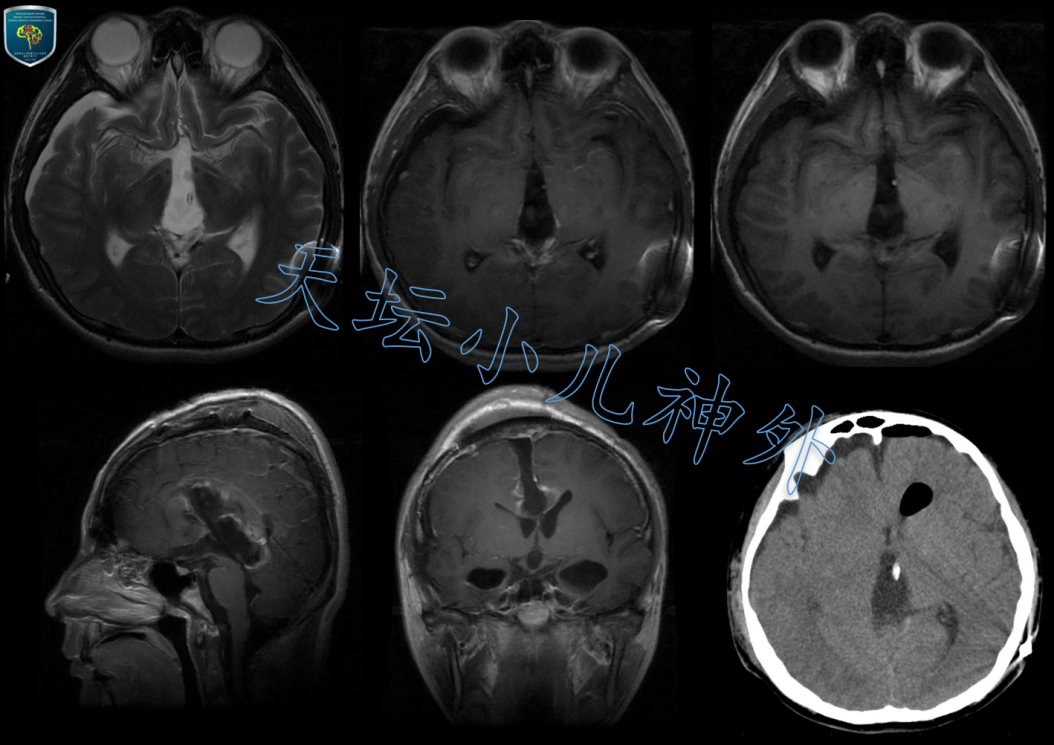

外科治疗儿童松果体区肿瘤的"天坛术式"值得大力提倡_松果体瘤_松果体

图片尺寸1054x745